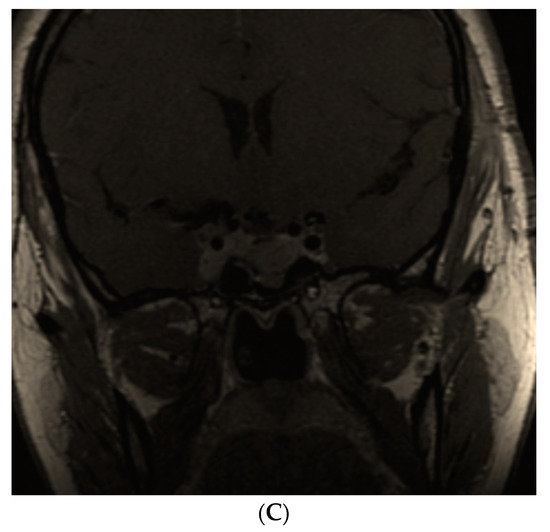

- Dicuonzo, F.; Purciariello, S.; De Marco, A.; Guastamacchia, E.; Triggiani, V. Inoperable Giant Growth Hormone-secreting Pituitary Adenoma: Radiological Aspects, Clinical Management and Pregnancy Outcome. Endocr. Metab. Immune Disord. Drug Targets 2019, 19, 214–220. [Google Scholar] [CrossRef]